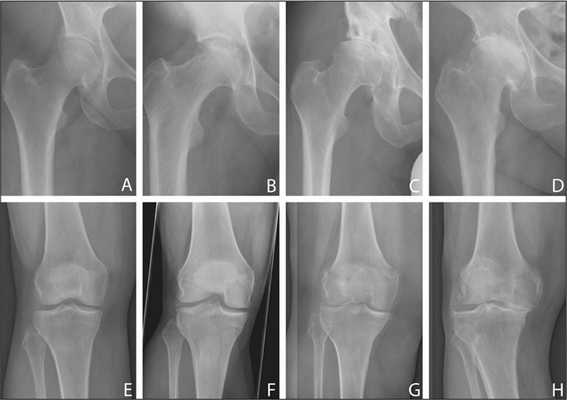

Деформирующий остеоартроз — одно из ведущих заболеваний опорно-двигательного аппарата. Он проявляется дегенеративно-дистрофическими изменениями суставных поверхностей. Частота встречаемости составляет от 3 до 12% среди взрослого населения. В этом показателе на первом месте стоит поражение тазобедренного сустава, а на втором - коленного.

Динамика болезни на рентгене.

Когда показано эндопротезирование

Основные показания к радикальным способам лечения - это неэффективность консервативных методик, наличие стойкого болевого синдрома, двигательных расстройств, нестабильности и выраженной деформации коленного сустава. К ситуации, когда операция оказывается единственным способом поддержания достойного качества жизни больного, приводит прогрессирование следующих патологий:

- деформирующий артроз 3-4 степени;